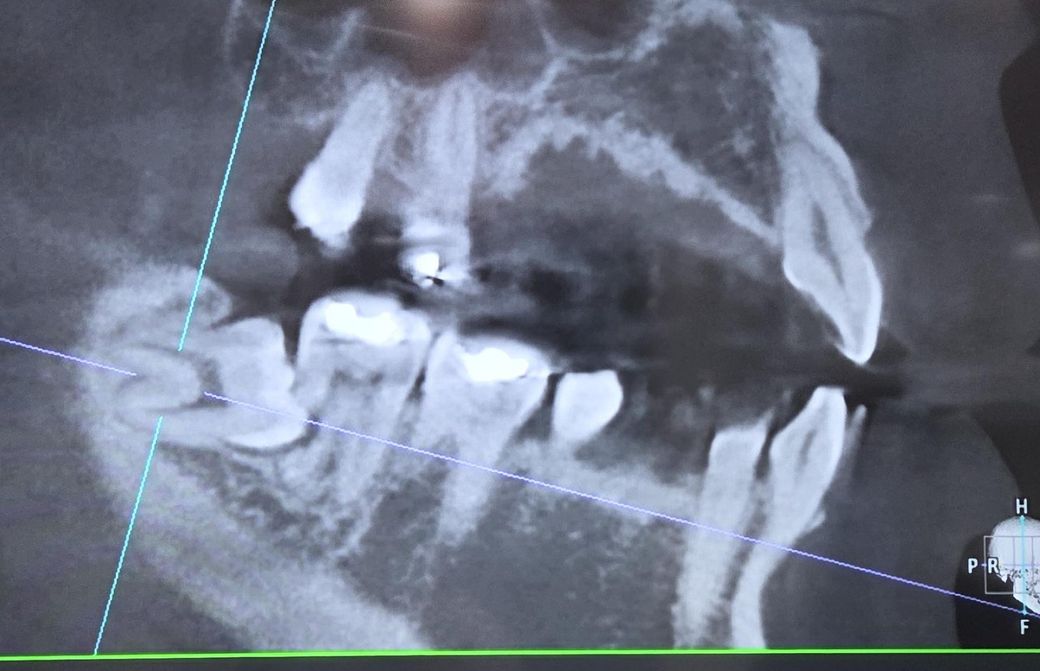

매복사랑니로 인해 어금니 뿌리가 녹았습니다

현재 매복사랑니로 인해 어금니 뿌리가 녹았다 하여 교정 혹은 임플란트를 해야한다고 얘기를 들었습니다

치아 뿌리가 사진에 보일정도로 녹은 상태라면 발치를 하고 임플란트를 하시는게 좋을것같습니다.

2. 지금으로선 두번째 어금니는 빼는것 외에 방법없습니다

3. 사랑니랑 두번째 어금니 빼고 임플란트를 추천합니다

우선 사랑니를 발치하고 난다음에 남아 있는 치아의 상태를 보고 결정을 해도 될것으로 생각됩니다.

큰 문제가 없다면 그냥사용할수도 있지만 불편감이 있거나 염증이 발생한다면 발치후 임플란트를 해야 할수도 있습니다.